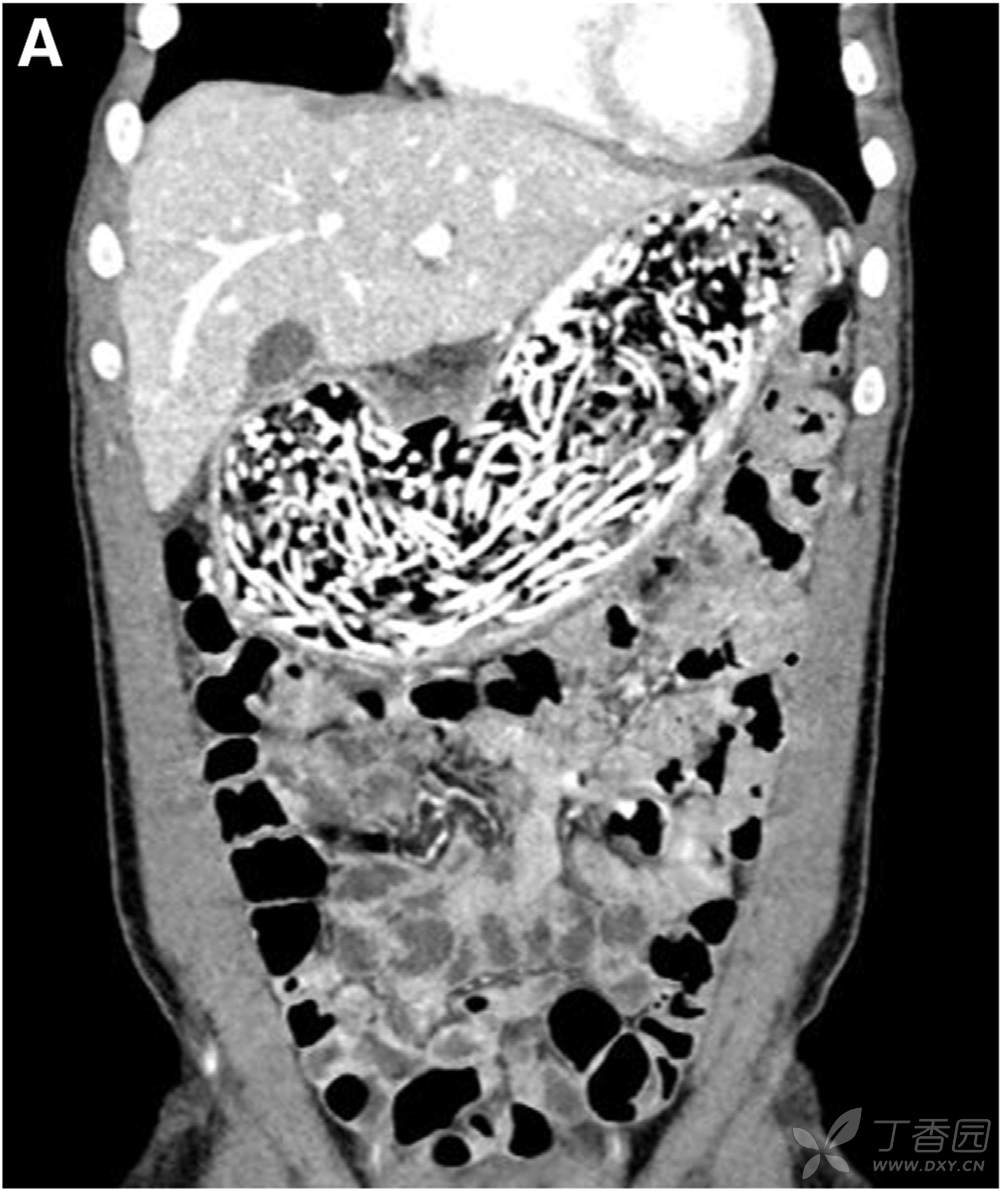

辅助检查:Hb 94g/L,MCV 75 fL,铁蛋白 7。WBC计数、血乳酸水平均正常。妊娠试验阴性。腹部CT所见如图。

请问:诊断是什么?下一步如何处理?

A 结核性腹膜炎 B 异食癖 C 蛔虫病 D 慢性肠梗阻